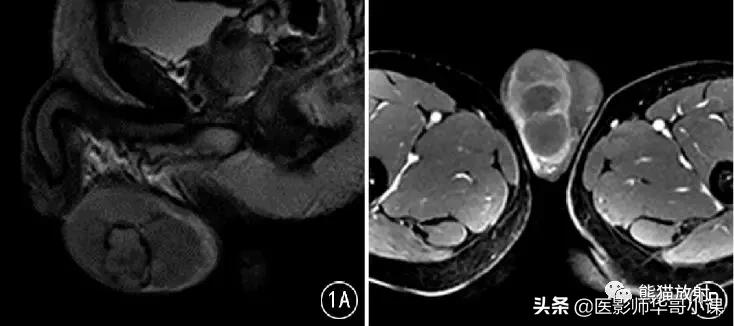

图2 男,31岁, 左侧*丸睾**混合型生殖细胞瘤 。T2WI示左侧*丸睾**混杂信号肿块;增强肿块明显不均匀强化。